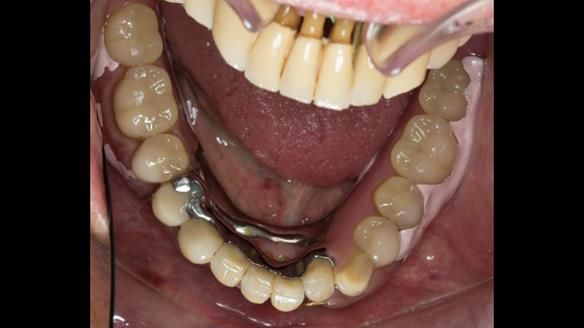

We began with the lower jaw.

Instead, we made a Scandinavian-style, metal-based lower RPD.

It was made promptly, then relined gradually over the following year

to optimise fit, comfort, and support.

A reflective note on the lower denture

It’s worth saying that the lower denture in this case was made in the early days of Rowan and me using the Scandinavian approach. Rowan cast the metalwork himself for this denture.

Looking back, we would make this denture more hygienic now. The design and finish would be more refined and delicate, particularly when compared with the upper metalwork, which was made later using Chris Hesketh’s chrome work. I will discuss this in detail at the study club.

That said, the lower denture worked beautifully. It did exactly what it was meant to do, even though, by today’s standards, it looks a little agricultural.